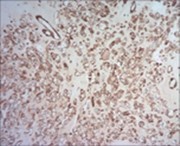

Figure 8.Parachordoma demonstrating immune reactivity to vimentin 16.

Parachordoma is immune reactive to cytokeratin CAM 5.2 and glial fibrillary acidic protein (50%). A subset of tumour cells are immune reactive to CD99 and smooth muscle actin (SMA). Stroma is intensely highlighted with an alcian blue stain wherein staining intensity is reduced following hyaluronidase digestion. Tumour cells are immune reactive to epithelial membrane antigen (EMA), CK8/18, S100 protein, calponin (50%), vimentin, type IV collagen and CD117 6.

Tumour cells are immune non reactive to CK1/10, cytokeratin AE1/AE3, CK20, CK7, CK19, CK12-17,smooth muscle actin (SMA), muscle specific actin (MSA), carcino-embryonic antigen (CEA), desmin, CD34, CD31, CD10, glial fibrillary acidic protein (GFAP), p63, TFE3, melan -A, brachyury, Human Melanoma Black-45 (HMB-45), D2-40 and α- inhibin.

Type IV collagen is immune reactive, envelops clusters of tumour cells and articulates a nest- like appearance 6, 7.